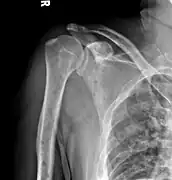

The diagnostic examination of a person with suspected multiple myeloma typically includes a skeletal survey. This is a series of X-rays of the skull, axial skeleton, and proximal long bones. Myeloma activity sometimes appears as "lytic lesions" (with local disappearance of normal bone due to resorption). And on the skull X-ray as "punched-out lesions" (pepper-pot skull). Lesions may also be sclerotic, which is seen as radiodense.[47] Overall, the radiodensity of myeloma is between −30 and 120 Hounsfield units (HU).[48] Magnetic resonance imaging is more sensitive than simple X-rays in the detection of lytic lesions, and may supersede a skeletal survey, especially when vertebral disease is suspected. Occasionally, a CT scan is performed to measure the size of soft-tissue plasmacytomas. Bone scans are typically not of any additional value in the workup of people with myeloma (no new bone formation; lytic lesions not well visualized on bone scan).

Skull X-ray showing multiple lucencies due to multiple myeloma

Multiple myeloma in the upper arm